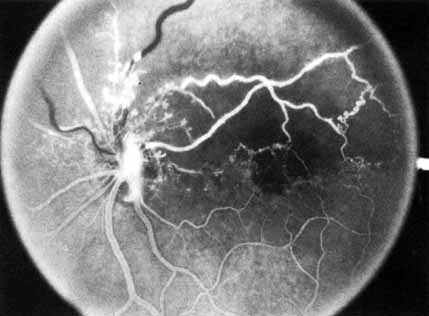

Fig. 1 A. “Blood and thunder” appearance of a central retinal vein occlusion. B. Intravenous fluorescein angiogram shows this occlusion is primarily ischemic or nonperfused. The fact that there is more nonperfusion in the inferior half of the fundus compared with the superior half is unusual.

Coats55 may have been the first to suggest that patients with central retinal vein occlusion fall into two groups: one with a dramatic, “blood and thunder” ophthalmoscopic appearance, loss of vision, and a poor prognosis (see Fig. 1); and the other with mild ophthalmoscopic changes, generally good visual acuity, and a relatively good prognosis (Fig. 2). Other investigators have commented on the difference in severity among central retinal vein occlusions, relying principally on the fluorescein angiogram to assess the severity of occlusion.56–59

The intravenous fluorescein angiogram pattern of an ischemic central retinal vein occlusion is usually characterized by a delayed filling time of the venous tree of the retina, capillary and venous dilation, and extensive leaking of fluorescein into the retina, particularly in the macular area and in the area adjacent to the larger venous trunks and capillary nonperfusion (see Fig. 3C and 3D; Figs. 4 and 5). Microaneurysms may not be noted at the time of initial occlusion, but are usually manifest shortly thereafter. Late-phase photographs show patchy extravascular areas of fluorescence and staining of the retinal veins. Fluorescence in the macula indicates capillary leakage and edema; this not only may account for much of the initial visual loss in the acute phase, but may also eventually result in permanent structural changes. Intravenous indocyanine green videoangiography may also be helpful in showing the arterial and venous flow alterations in this condition.322

Fig. 5 Fluorescein angiogram of acute ischemic retinal vein occlusion. Capillary nonperfusion is essentially 100%.